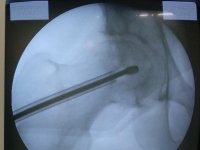

У Ковелі лікарі провели складну операцію на серці 53-річному лучанину

Відтепер у грудях лучанина працює своєрідна «бригада швидкої допомоги»